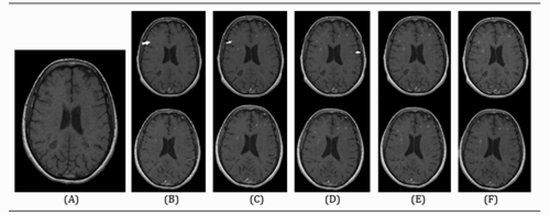

Comparison of Gadovist and Magnevist in Brain Magnetic Resonance Imaging of Multiple Sclerosis Patients with an Acute Attack

Background: The use of an appropriate contrast agent performs a major role in brain Magnetic resonance imaging (MRI) of Multiple sclerosis (MS) patients. Objectives: The present study aimed to make a comparison between the diagnostic values of Gadovist and Magnevist considering the successive imaging times in contrast-enhanced brain MRI of MS patients. Methods: A total of 62 relapsing-remitting MS patients (56 females, mean age of 31 years) were enrolled in the present study. All of them underwent two sessions of standard contrast-enhanced brain MRI upon enrollment and 48 h later. The participants were randomly assigned to each contrast agent. T1-weighted (T1W) images were taken 30 sec, as well as 5, 10, 15, and 30 min after the contrast injection. For all of the images, two neuro-radiologists who were blinded to the contrast type counted the number of plaques in the brain. In addition, for the enhanced plaques larger than 10 mm, the signal intensity (SI) was determined using its region of interest. Results: The mean plaque number significantly increased from 30 sec to 15 min for both contrasts separately (P<0. 001). Nonetheless, the slight increases in the mean plaque number from 15-30 min for both Gadovist and Magnevist were not statistically significant (both PValues>0. 25). The mean plaque number in the Gadovist group was higher, compared to that in the Magnevist group at both 15 and 30 min, and the differences were statistically on the borderline (both P-Values=0. 07). The mean SI of enhanced plaques gradually increased in the course of imaging in both contrast groups. Except for 30 sec, in all other time sessions, the mean SI was higher in Gadovistenhanced MR images, compared to Magnevist-enhanced MR images (P<0. 01). Conclusion: As evidenced by the obtained results, Gadovist showed a relatively better diagnostic value for brain MRI of MS patients. Furthermore, the findings suggested that it is cost-effective to take MRI only up to 15 min (instead of 30 min) after contrast injection in both agents